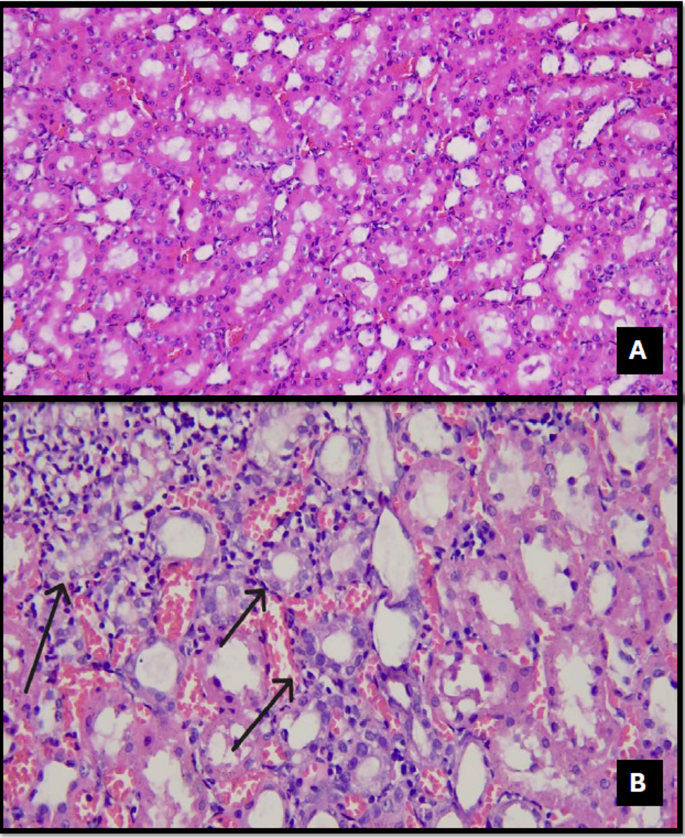

In the control group, renal structures were consistently within normal morphological limits across all histopathological examinations, with no evidence of inflammation, necrosis, or degeneration (Figs. 1, 2, 3, 4, 5, 6, 7, 8 and 9).

Vasa recta leukocyte infiltration (VRLI) (Fig. 4) was observed in 12.5% of the DEX group, 62.5% of the TAC group, and 75% of the TAC + DEX group. A statistically significant difference was detected among the groups (p = 0.007) (Table 3).

Tubular dilation (Fig. 7) was observed in 16.7% of the Control (SF) group, 50% of the DEX group, 87.5% of the TAC group, and 100% of the TAC + DEX group. A statistically significant difference was detected among the groups (p = 0.003) (Table 3).

Loss of the brush border (Fig. 8) was observed in 87.5% of the TAC group and 100% of the TAC + DEX group. A statistically significant difference was detected between the groups (p = 0.019) (Table 3).